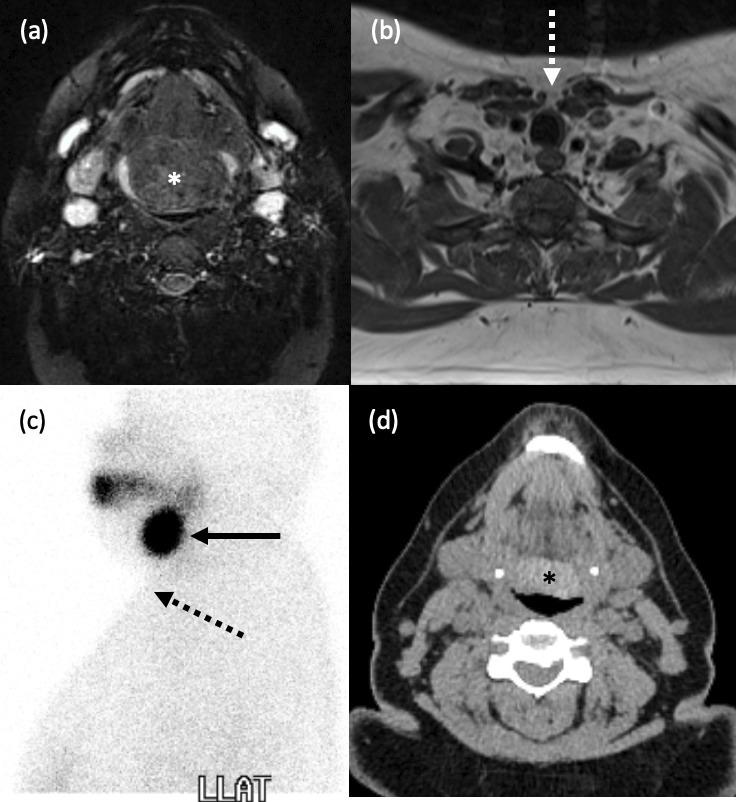

咽病理学的影像学表现。

Imaging of pharyngeal pathology.

The pharynx plays a significant role in swallowing and speech, and this is reflected in both its complex anatomy and degree of physiological motility. Patients who present with pharynx-related symptoms such as sore throat, globus, dysphagia or dysphonia will usually undergo visual and nasal endoscopic examination in the first instance. Imaging is frequently required to supplement clinical assessment and this typically involves MRI and CT. However, fluoroscopy, ultrasound and radionuclide imaging are valuable in certain clinical situations. The aforementioned complexity of the pharynx and the myriad of pathologies which may arise within it often make radiological evaluation challenging. In this pictorial review, we aim to provide a brief overview of cross-sectional pharyngeal anatomy and present the radiological features of a variety of pharyngeal pathologies, both benign and malignant.

咽在吞咽和言语中起着重要作用,这反映在其复杂的解剖结构和生理运动程度上。出现咽痛、咽部异物感、吞咽困难或发音困难等咽部相关症状的患者通常首先进行视诊和鼻内镜检查。影像学检查常需要补充临床评估,通常包括 MRI 和 CT。然而,透视、超声和放射性核素成像在某些临床情况下具有重要价值。上述咽的复杂性和可能发生的多种病理改变常常使影像学评估具有挑战性。在本影像学综述中,我们旨在简要概述咽的横断解剖结构,并介绍各种良性和恶性咽病变的影像学特征。